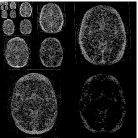

The SNR values of the different reconstruction results are shown in Table 1. Figure 4 shows the baseline and follow-up pomelo images and the reconstruction results. As expected, reconstruction results improve as the acceleration ratio decreases, for all methods. The major differences between the baseline and follow-up scans consist of two enhancing regions (marked in arrows), due to the injection of a contrast agent before the acquisition of the follow-up scan.

In terms both image resolution and SNR, LACS-MRI outperforms TCS-MRI and CS-MRI, by exhibiting significantly improved recovery of the image at 4-fold acceleration, which also allows to identify changes versus the baseline scans, i.e. the two enhanced areas. Although both TCS-MRI and LACS-MRI utilize temporal similarity in the reconstruction process, this experiment emphasizes the advantage of embedding weighted-CS and adaptive sampling. Together with the weighting mechanism, the sampling locations (shown in the bar next to each image) which were chosen adaptively by LACS-MRI, lead to improved reconstruction results versus the pure random sampling used in CS-MRI and TCS-MRI.